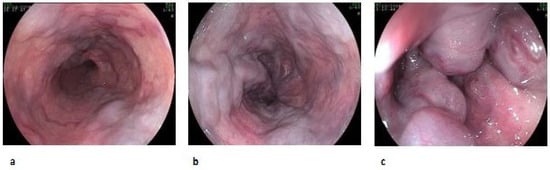

Esophageal varices are classified by size (small, medium, or large) and by the presence of red wale marks (Figure 1, Table 2) [12], while GV are classified as gastroesophageal varices (GOV) or isolated gastric varices (IGV) (Figure 2, Table 3) [13].

Figure 1. Esophageal varices according to size: F1 (a), F2 (b), F3 (c).